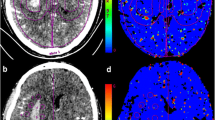

Postprocessing of raw CTP source images was performed on CT Perfusion 4D software of a standard Advantage Workstation (AW 4.7, GE Healthcare). The software performed head motion correction and generated mathematical descriptions of time-density curves for each brain voxel. Arterial input and venous output were derived from the ipsilateral anterior cerebral artery and the superior sagittal sinus. The parametric maps PS were calculated by the same software using a deconvolution algorithm. The PS value is a measure used to assess the rate of contrast leakage from the intravascular to extravascular space through a disrupted BBB. Regions of interest (ROIs) were drawn using planimetric techniques on raw CTP images and were transferred to corresponding PS maps. At the image slice with the maximum hematoma area, 8 approximately equidistant 80mm2 round ROIs were marked within the 1 cm boundary region outside the hematoma. Contralateral mirror ROIs were constructed by reflecting the ROIs around hematoma across the brain midline (Fig. 1). Mean PS values were calculated by averaging the PS values in 8 ROIs in each brain hemisphere. To minimize the impact of patient level heterogeneity, relative PS (rPS) value was calculated as a ratio of ipsilateral to contralateral mean PS. Large blood vessels, ventricles, image artifacts, bones, and calcifications were avoided while drawing the ROIs to ensure more accurate and repeatable results. This CTP post-processing was independently completed by two experienced radiologists.

Graphical illustration of the regions of interest (ROIs) drawn on computed tomography perfusion baseline image (a) and corresponding permeability-surface area product map (b). The region between two red lines defines a 10mm zone surrounding the hematoma. Yellow circles define ROIs drawn in the perihematomal region